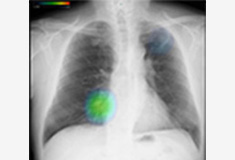

- 一般撮影検査

- エックス線を診察したい部位にあて、身体を透過した情報から疾患や骨折の有無を調べることができる検査で、画像診断のおおもととなる検査です。当院ではフラットパネルディテクター(FPD)装置を導入していますので、低被ばく線量でありながら高精細な画像を提供しています。

-

胸部X線画像

胸部 AI 解析画像